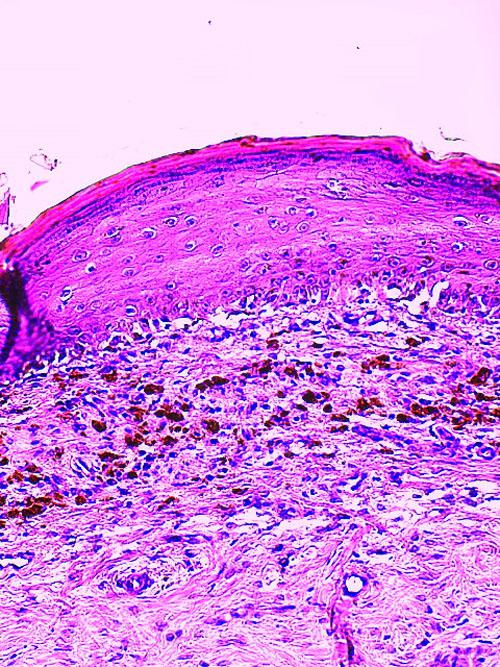

Une griffe a fait l’objet de recoupes multiples et a été examinée après coloration standard Hemalun-éosine et réaction au PAS.

La structure histologique de la griffe est globalement préservée. L’étui corné montre une structure histologique subnormale. La matrice unguéale peut être discrètement hyperplasique. De façon segmentaire, son assise basale est discrètement grignotée par une exocytose de petits lymphocytes matures associés à la présence de petits foyers de dégénérescence hydropique des cellules de l’assise basale et la présence de quelques corps apoptotiques. De rares images de satellitose sont également remarquées. Par endroits, la jonction dermo-épidermique est manifestement fragilisée avec l’apparition de petites fentes à la jonction dermo-épidermique. Le derme sous-jacent montre une infiltration cellulaire inflammatoire lichénoïde discrète ponctuelle essentiellement lymphoplasmocytaire. La lame osseuse de la troisième phalange montre une structure histologique normale.

Absence d’élément figuré pathogène, parasitaire ou fongique et en particulier PAS positif.

Photo 6 : histologie de l’onyxis

Conclusion : l’aspect histologique est celui d’un discret onyxis d’interface lymphoplasmocytaire segmentaire.

Aspect lésionnel concordant avec l’hypothèse clinique proposée d’onychodystrophie lupoïde. Absence d’élément figuré pathogène, parasitaire ou fongique. Absence de lésion de vasculopathie/vascularite.